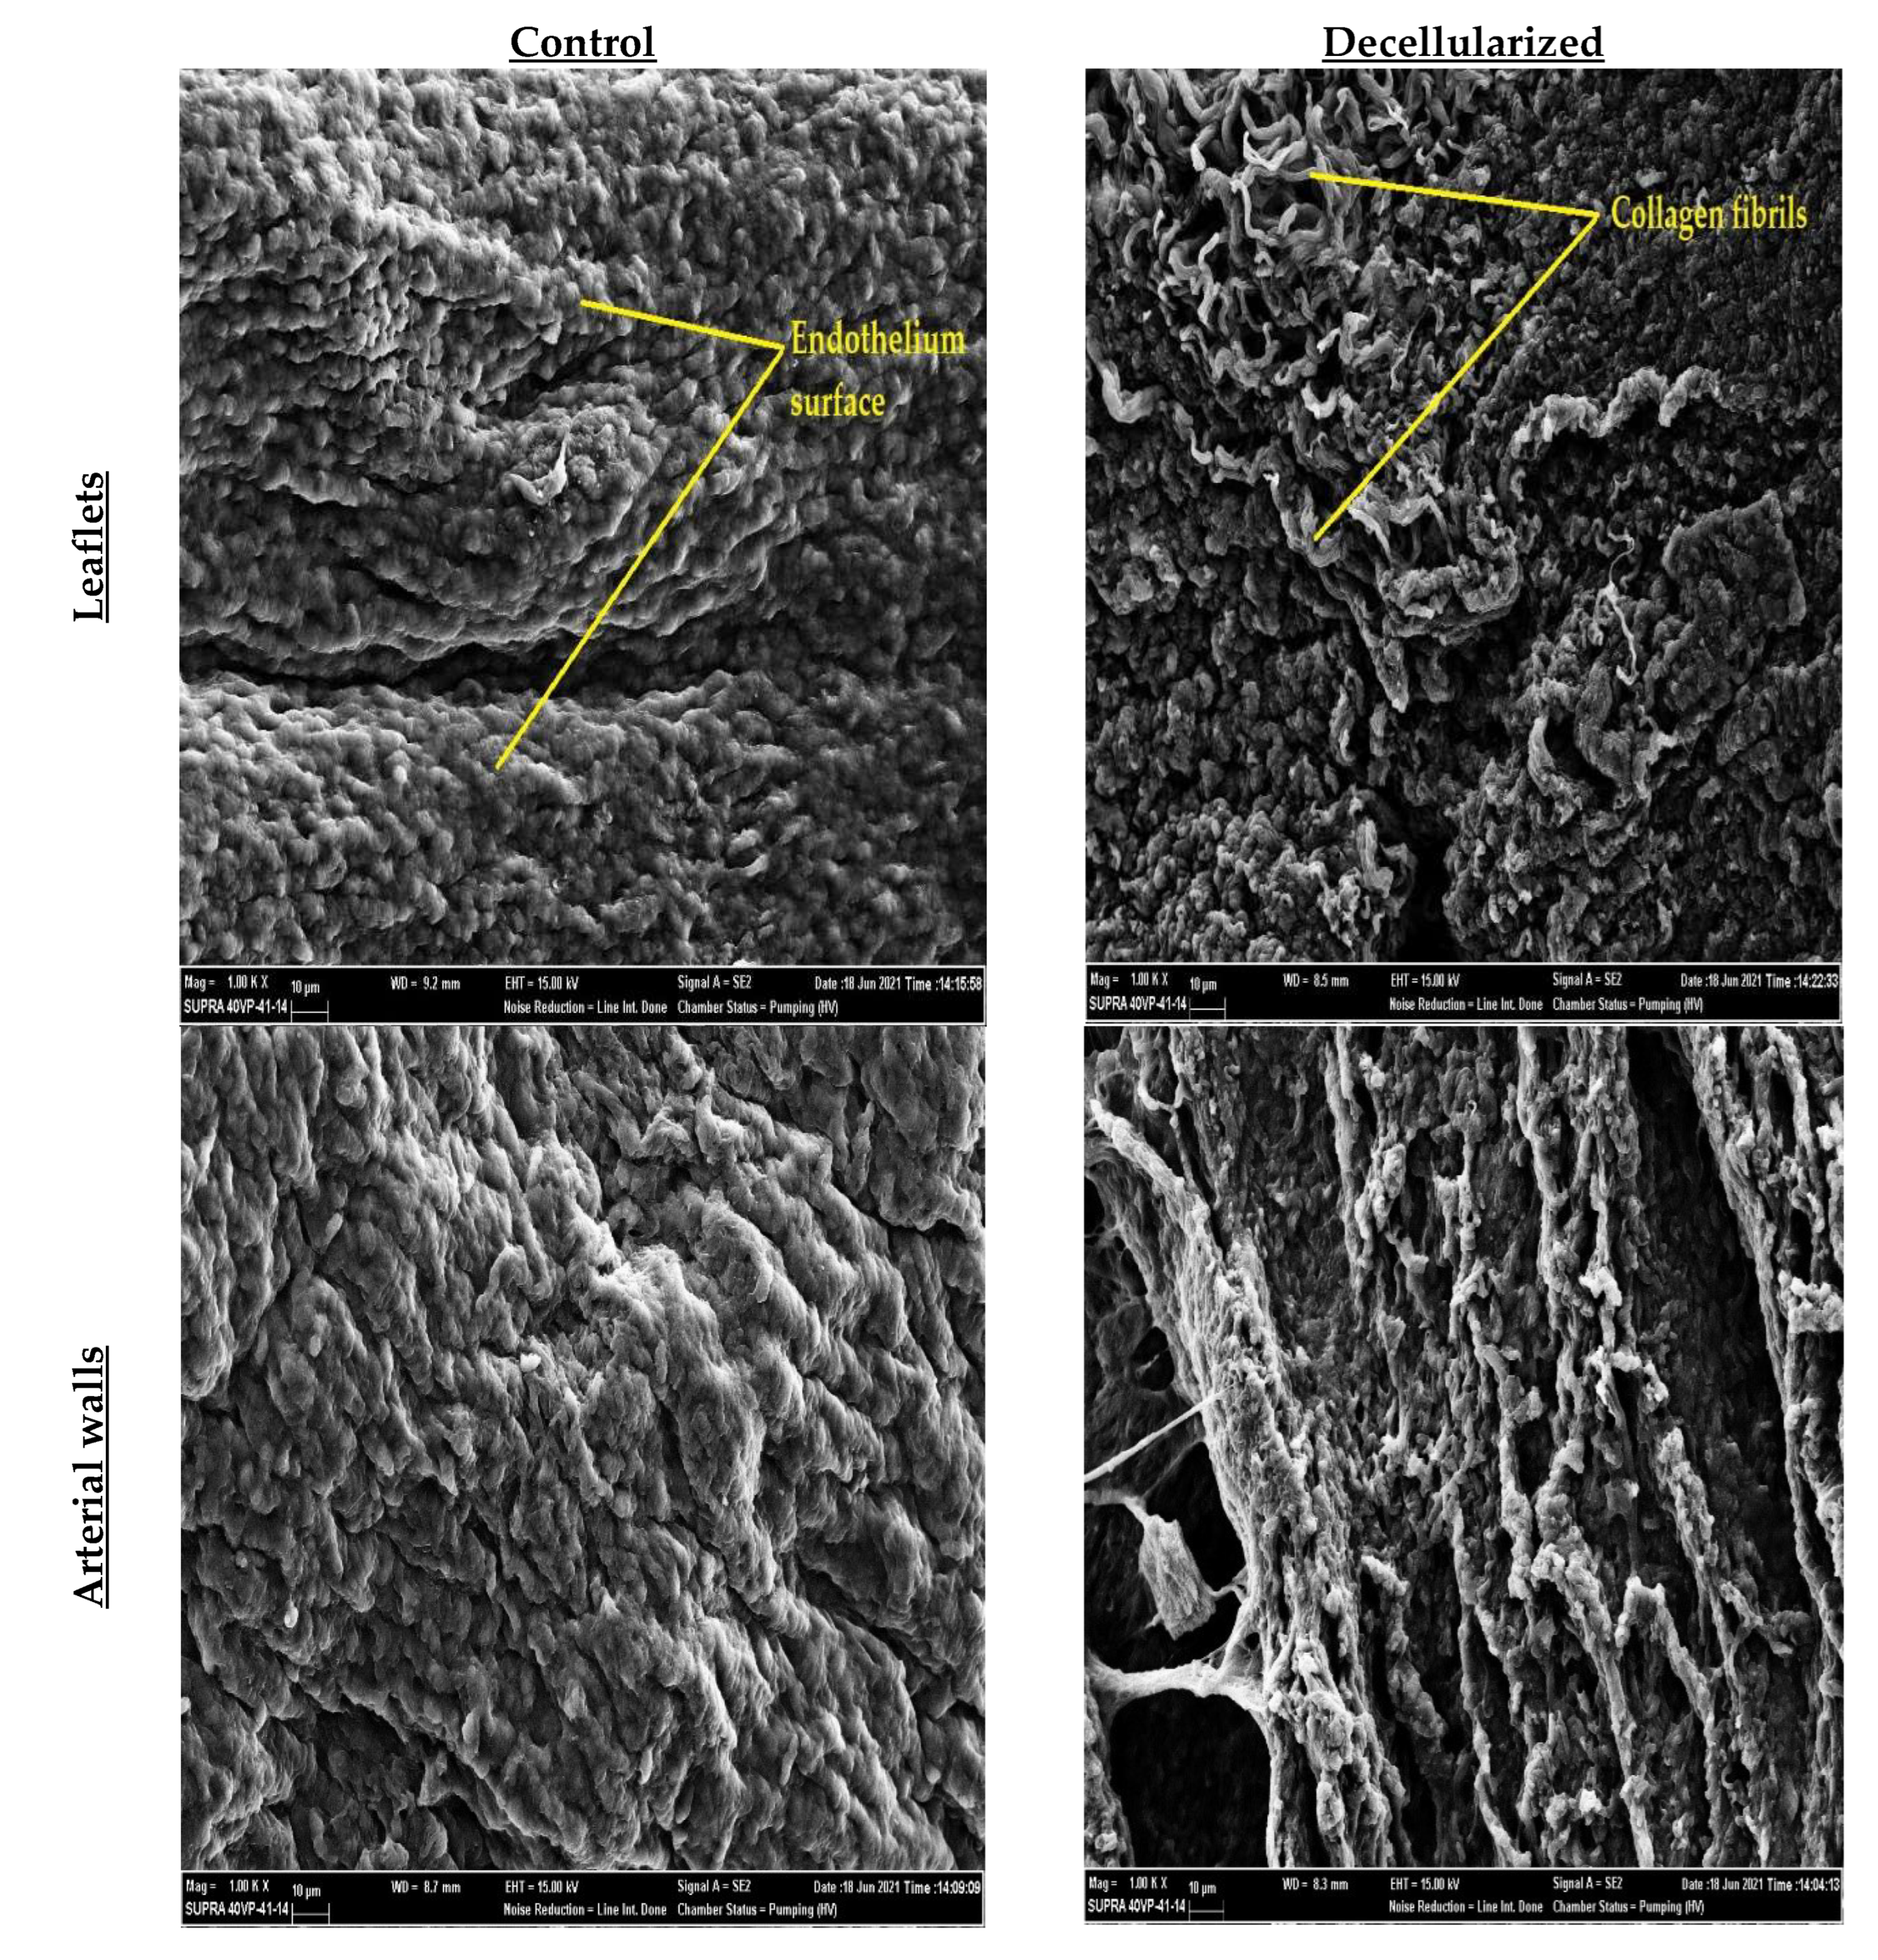

2.4. SEM Imaging